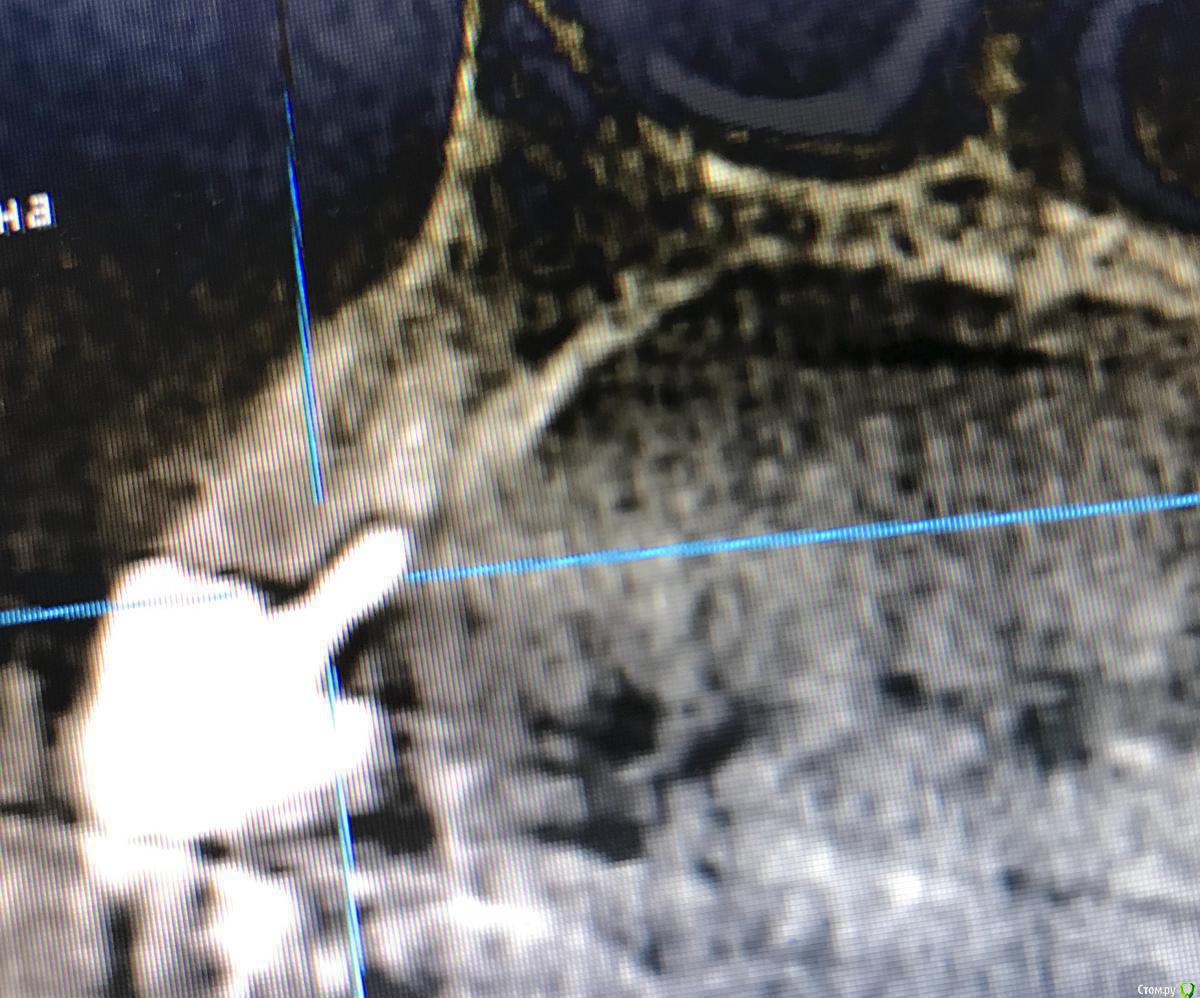

DenisV Опубликовано 21 марта, 2018 Поделиться Опубликовано 21 марта, 2018 Уважаемые коллеги планируется удаление и установка имплантата 3.8 10 dentium можно ли будет обойтись без костной и тканевой аугментации? Ссылка на комментарий

DenisV Опубликовано 21 марта, 2018 Автор Поделиться Опубликовано 21 марта, 2018 Уважаемые коллеги планируется удаление и установка имплантата 3.8 10 dentium можно ли будет обойтись без костной и тканевой аугментации? Ссылка на комментарий

колесников Опубликовано 21 марта, 2018 Поделиться Опубликовано 21 марта, 2018 Можно,но не нужно. Размеры оптимальные. Немедленная нагрузка показана. Стремитесь к винтовой фиксации,длинный Имплант в этом случае будет сложно расположить. Удалять атравматично,лоскут не откидывать, Сст вестибулярно 1 Ссылка на комментарий

колесников Опубликовано 21 марта, 2018 Поделиться Опубликовано 21 марта, 2018 (изменено) Чтобы отвертка не уперлась в режущий край,ставить лучше более вертикально,Апекс в этом случае будет близко к вестибулярной компактной пластинке ,после нагрузки может быть окончатся резорбция. Мне кажется, 10 мм с заглублением, самое то. Изменено 21 марта, 2018 пользователем колесников 1 Ссылка на комментарий